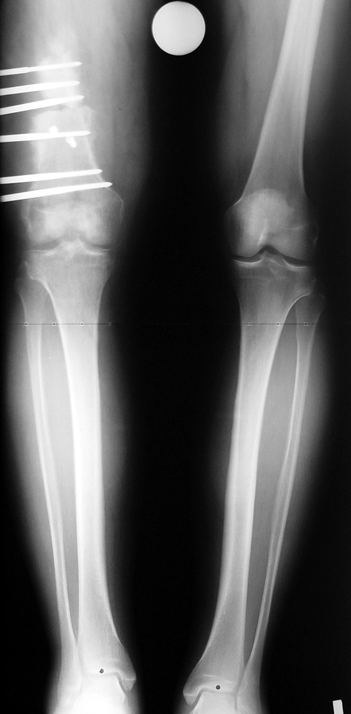

Appropriate radical debridement necessitates excision of all necrotic bone and soft tissues, and frequently causes instability at the involved extremity. The remaining bone and soft tissue defect has to be fixed and reconstructed. The distraction osteogenesis method of Ilizarov is used successfully for achievement of union, correction of the deformity, elimination of limb length inequality and reconstruction of segmental bone defects.

The duration of external fixation (external fixation index) depends on the amount of distraction required, and the extremity is prone to complications during this period. After the distraction phase is completed, the external fixator remains in place during the consolidation phase, which lasts twice as long as the distraction phase; but this period is hardly tolerated. If the external fixator is removed before sufficient consolidation is achieved, fractures, deformity and shortness will be the result. In our department, ‘lenghthening over nail’ method is used in order to decrease the external fixation index and increase patient comfort and activity level. In this method, the intramedullary nail is statically locked after the completion of the distraction phase, and external fixator is removed. The extremity is stabilized by the intramedullary nail during consolidation phase. In this way, complications due to long external fixation index or early removal of the external fixator are avoided.

Case 2